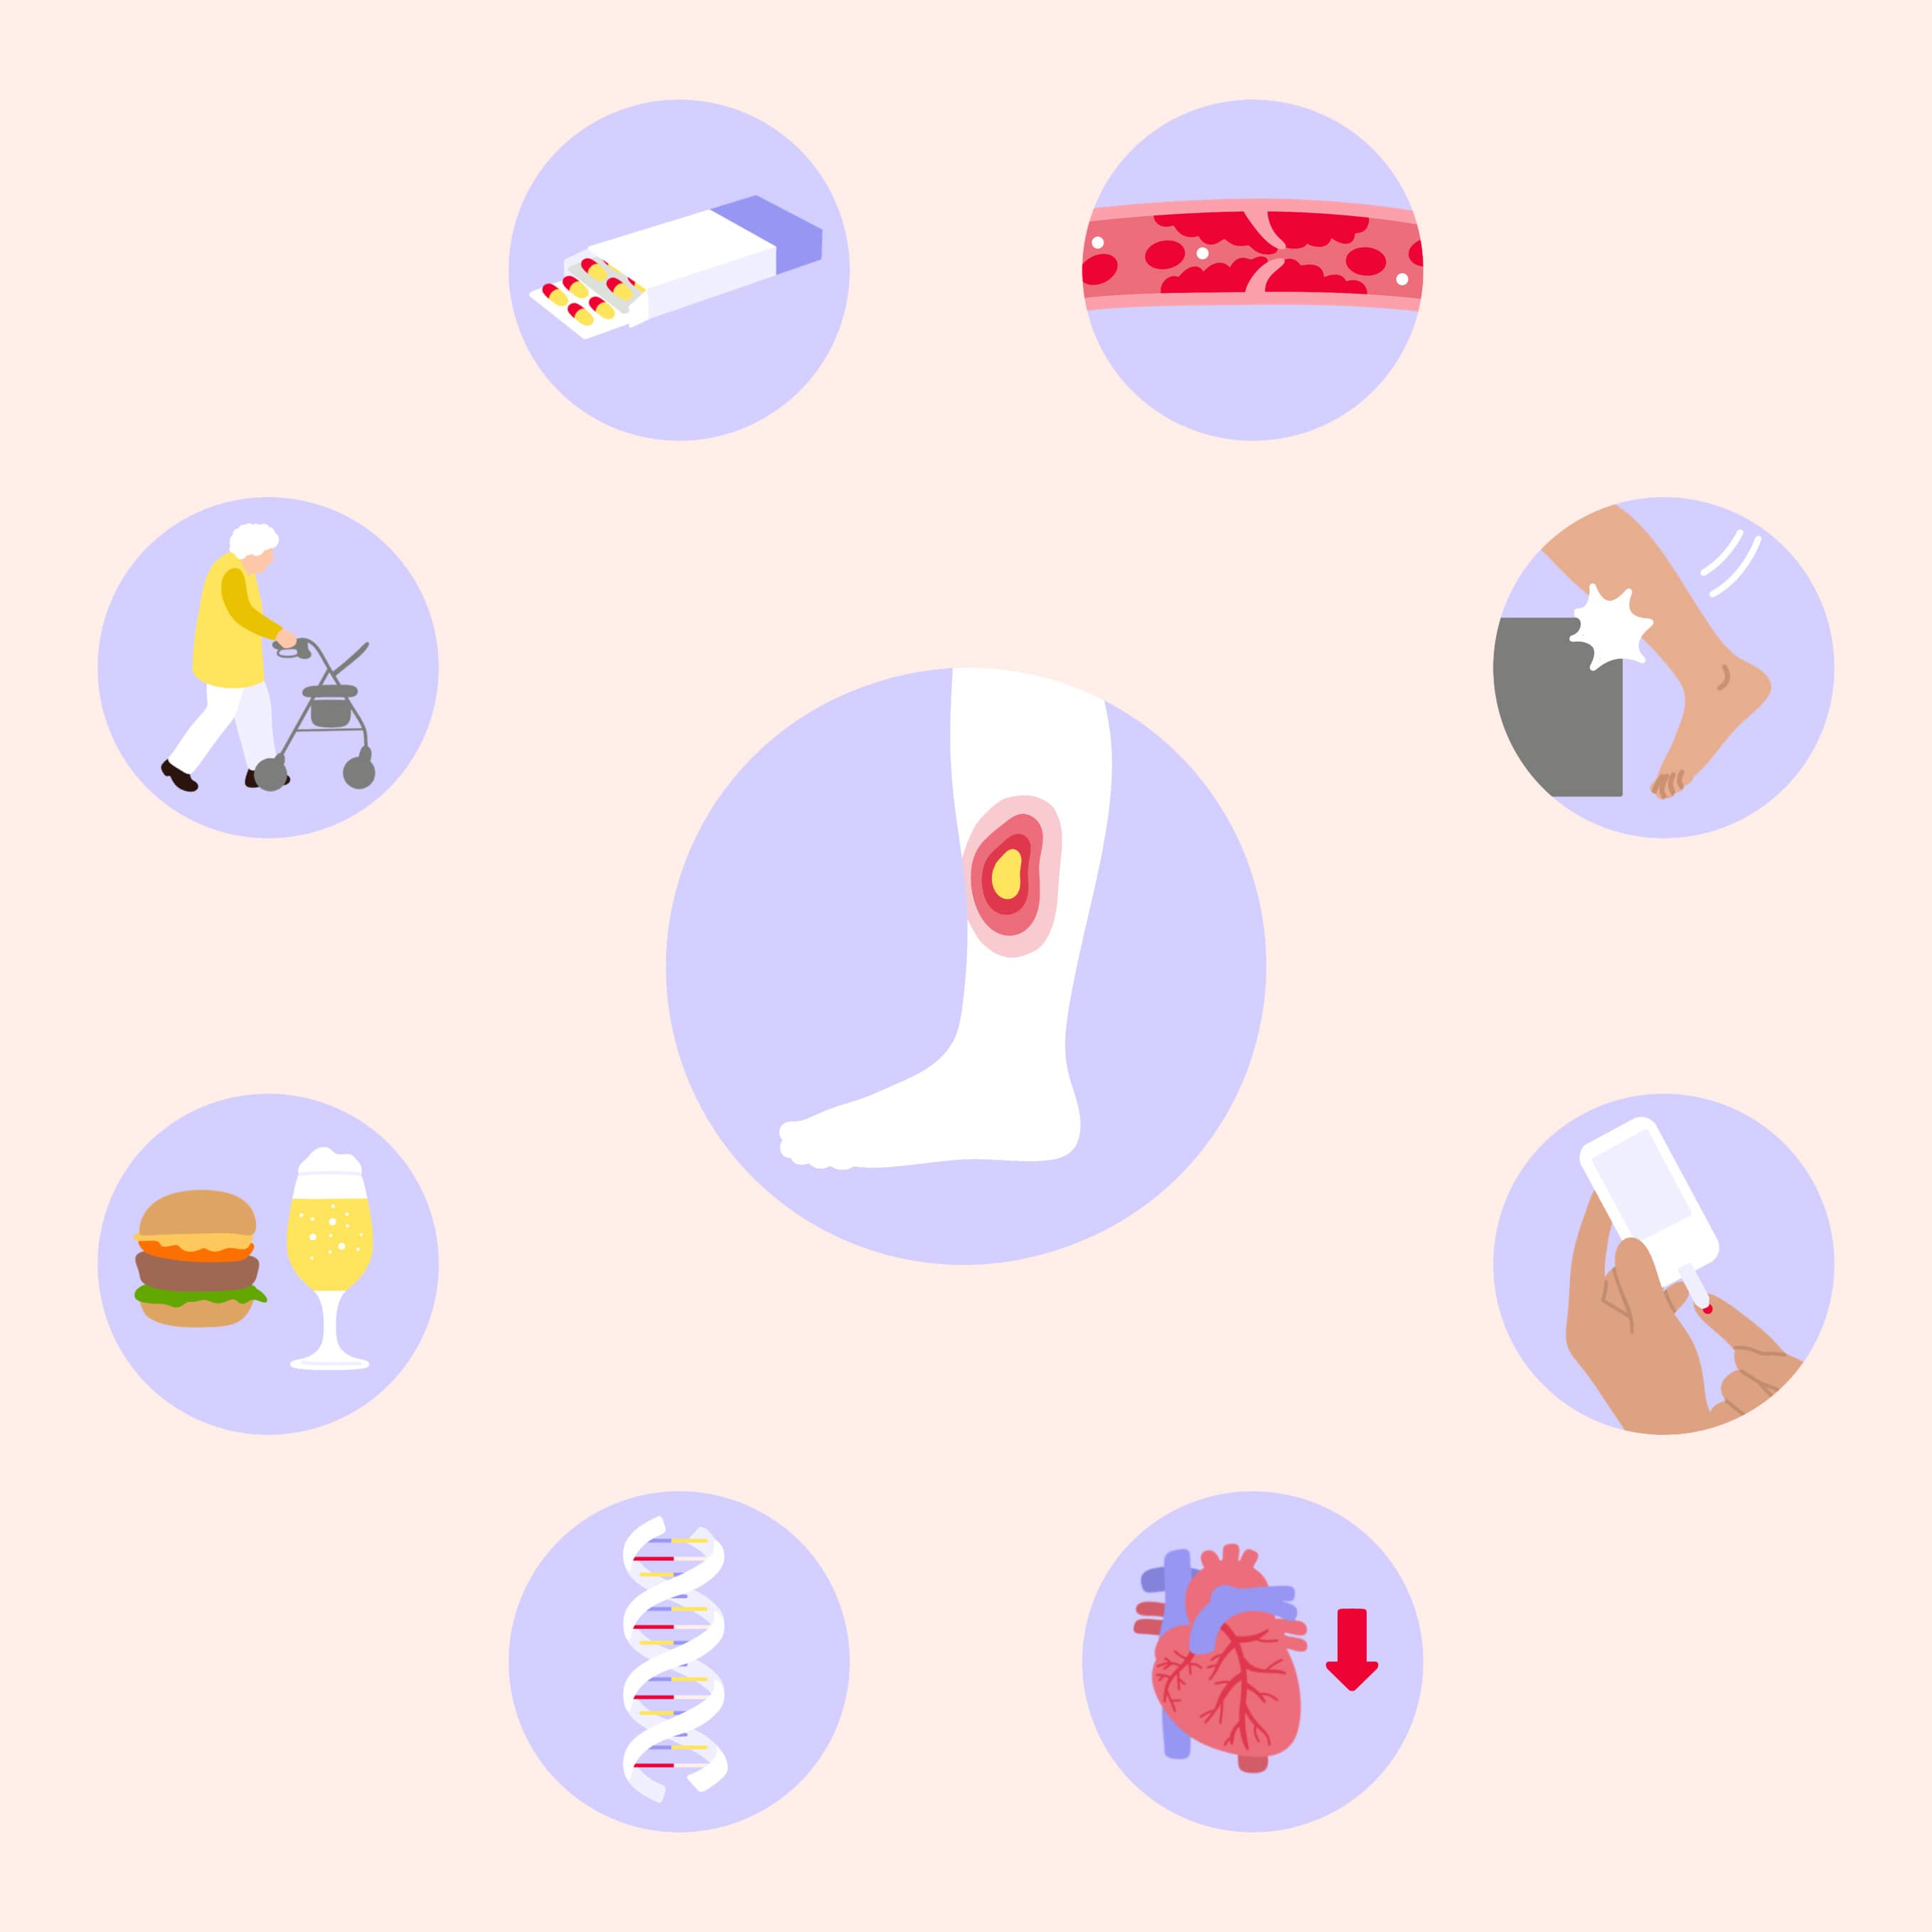

Das Ulcus cruris hat unterschiedliche Ursachen. Erkrankungen und andere Faktoren, die dafür verantwortlich sein können, sind unter anderem:

- Eine gestörte Durchblutung der Venen, z. B. durch den Verschluss der Becken- oder der tiefen Beinvenen (postthrombotisches Syndrom), Varikose bei unbehandelten Krampfadern (Varizen) oder bei einer chronisch-venösen Insuffizienz (CIV) als schwerster Verlaufsform, Bluthochdruck (Hypertonie, Ulcus cruris hypertonicum)

- Unfälle

- Grunderkrankungen, z. B. Zuckerkrankheit (Diabetes mellitus) oder Herzinsuffizienz, bestimmte Tumorformen wie das Basalzellkarzinom oder Plattenepithelkarzinom, Gerinnungsstörungen, Sichelzellanämie

- Genetische Veranlagung, z. B. Klinefelter-Syndrom

- Lebensstilfaktoren, z. B. Rauchen, Alkohol, ungesunde Ernährung, z. B. mit einem zu hohen Anteil an Kohlenhydraten (in erster Linie aus Industriezucker)

- Alter, z. B. tritt das offene Bein bei Menschen unter 40 Jahren seltener auf als bei älteren ab 75

- Medikamente

- Infektionen, z. B. Syphilis, Leishmaniose